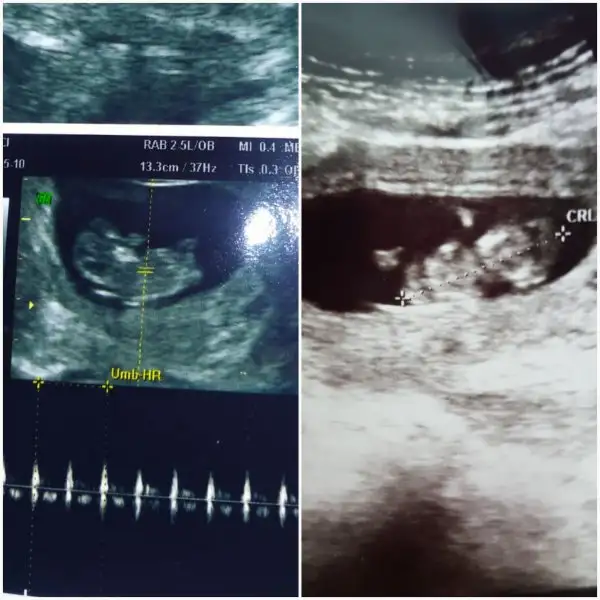

Evet 12+3 görüntüsü benimki ama nub 10 da oluşmaya başlıyo 12 tamamen tAmamlanıyo diye biliyorum ben

Mesela bu görüntüde benimkini açıklıyo. Ben bu acıdan görebildim cunku. Üstten ve bacak arasından. Benımkını yandan görmedim ben.